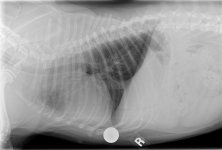

PS Attached is an excel file with the info from above, as well as a calendar grid of the same information, and blood test results from the 8th and 10th. We've requested the blood test results from the Surgeon (which would be before she got sick) and hope to have those by tomorrow. Also, I've attached the x-rays our regular vet took on the 10th.

PS Attached is an excel file with the info from above, as well as a calendar grid of the same information, and blood test results from the 8th and 10th. We've requested the blood test results from the Surgeon (which would be before she got sick) and hope to have those by tomorrow. Also, I've attached the x-rays our regular vet took on the 10th.